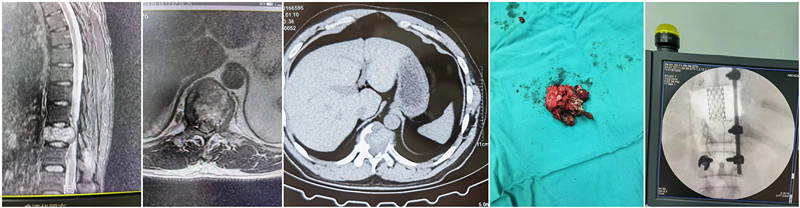

患者男性,35岁,因腰背痛前来就诊,穿刺活检考虑骨巨细胞瘤,该肿瘤如果切除不完全,极易复发,为尽可能减少复发的可能,在做好充分术前准备的情况下,1月22日,我院驻疆专家杨宝辉副主任医师为患者实施了全脊椎切除术(En-bloc)术,术中将后方椎体附件结构完整取出,然后保护脊髓,通过双侧会师,达到椎体前方,完整旋出椎体部分。手术历经5小时,出血1000ml,术后患者双下肢肌力与术前一致,均为IV级。